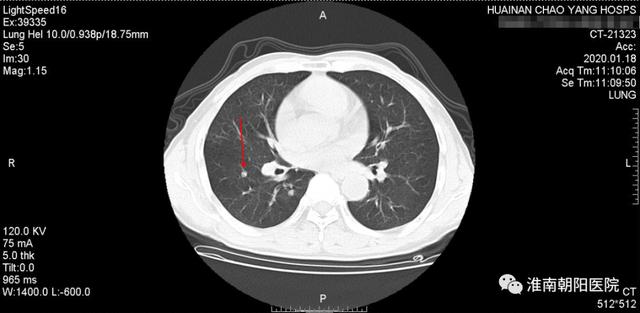

10 月底复查 CT 病灶缩小,病情明显好转。

(图为 10 月份复查 CT 片,可以看见肿瘤小了)